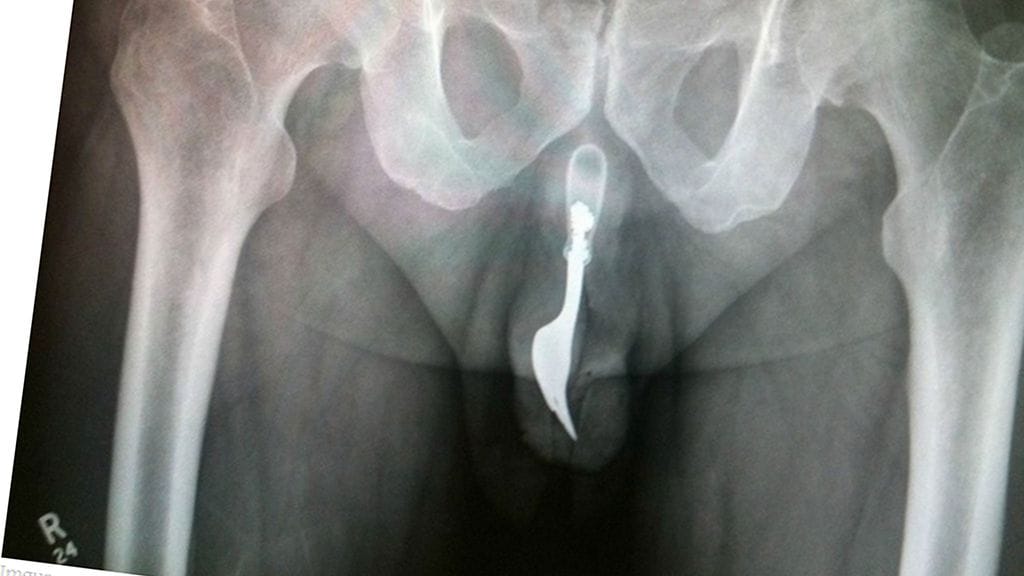

Erikoiset röntgenkuvat saavat ihmettelemään vain yhtä asiaa: voivatko ihmiset oikeasti olla näin typeriä?

Mikä menee sisään, ei välttämättä tule ulos ihan itsestään. Unilad-sivuston julkaisemat röntgen-kuvat asioista, joita himokkaat miehet ovat sisäänsä tunkeneet, eivät ensituntumalta vaikuta edes mahdollisilta.